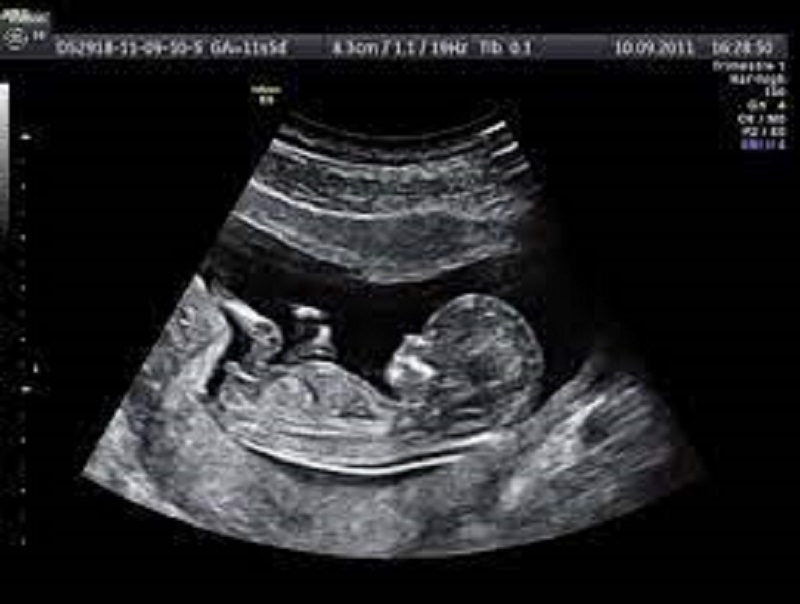

Thai nhi trong 3 tháng đầu tiên phát triển như thế nào?

Ở giai đoạn 3 tháng đầu của thai kỳ, thai nhi sẽ chuyển từ phôi thai thành một cơ thể hoàn chỉnh. Em bé lúc này có một số đặc điểm nổi bật sau:

Các ngón tay, ngón chân đã phát triển rõ ràng,

Xuất hiện mí mắt và tóc,

Cổ, cằm, đôi tai dần hoàn thiện,

Bắt đầu có những chuyển động nhẹ nhưng mẹ rất khó nhận ra.

Như đã nói ở trên, đôi tai của bé vào tháng thứ 3 đã dần được hoàn thiện. Tức là thính giác của bé đã phát triển mạnh. Vì vậy em bé hoàn toàn có thể nghe được những âm thanh bên ngoài. Chưa kể, nước ối còn là môi trường truyền âm rất tốt.